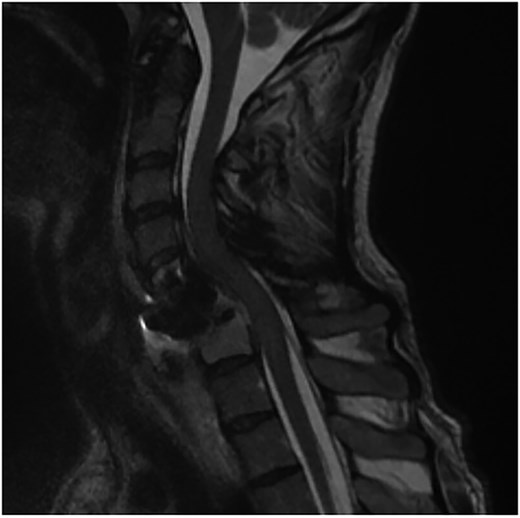

A 35-year-old male presented with a month-long history of dysphagia, severe headache, and posterior neck pain that radiated to the occiput. His medical history was significant for cervical surgeries, including an anterior cervical discectomy and fusion (ACDF) at C5/C6 one year and two months ago (Fig. 1). Shortly thereafter, the patient underwent revision surgery along with posterior plating from C5 to T1 due to osteomyelitis, worsening cervical deformity, and retropharyngeal abscess (Fig. 2). Initial workup included a noncontract computed tomography (CT), demonstrating increased gas density at C6 corpectomy site and post cricoid region (Fig. 3). A swallow study was obtained based on suspicion of a perforation and demonstrated extraluminal leakage of contrast posteriorly at the C6 level, consistent with initial CT (Fig. 4). Surgery included removal of the anterior and posterior hardware and esophageal repair. Although initially the esophageal injury was suspected to be related to the hardware, intraoperatively, it was found the instrumentation was not in communication with the esophagus. This confirmed the perforation was unrelated to direct injury from the cervical hardware construct, which was intact. The esophagus was repaired with a pectoralis flap. The postoperative course was uneventful, and the patient was discharged home after one week. The patient later died due to severe complications of substance abuse unrelated to the operation.

Sagittal T2-weighted MR of prior retropharyngeal abscess that led to revision and posterior plating from C5 to T1.